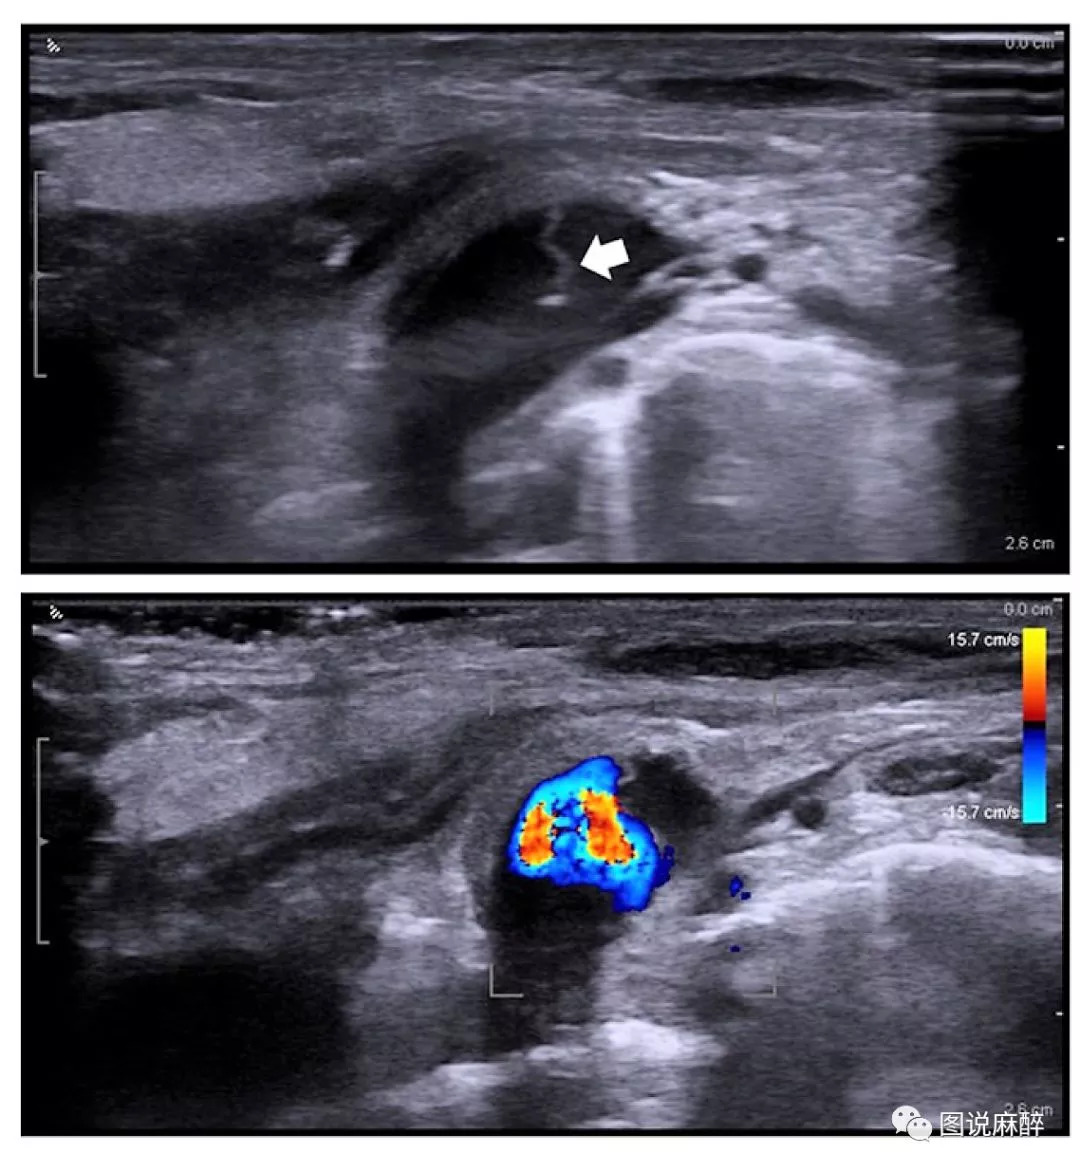

上:颈内静脉的2D超声图像,箭头所指为一瓣状物;

下:多普勒图像,横截面瓣状物右侧无血流;

术后,超声扫查在左颈内静脉内发现瓣状物(如上图),位于穿刺点下方5cm,担心可能是血栓或者静脉内膜撕裂形成的夹层。但穿刺过程顺利,夹层发生的可能性极小,并且右侧颈内静脉超声也发现类似的结构,遂决定先观察。

术后一周,再行超声检查,未见变化,多学科会诊后共同认为是颈内静脉瓣(IJV valves)。

声像图上颈静脉瓣呈带样强回声,根部附着于静脉壁上,瓣膜游离缘指向心脏方向。